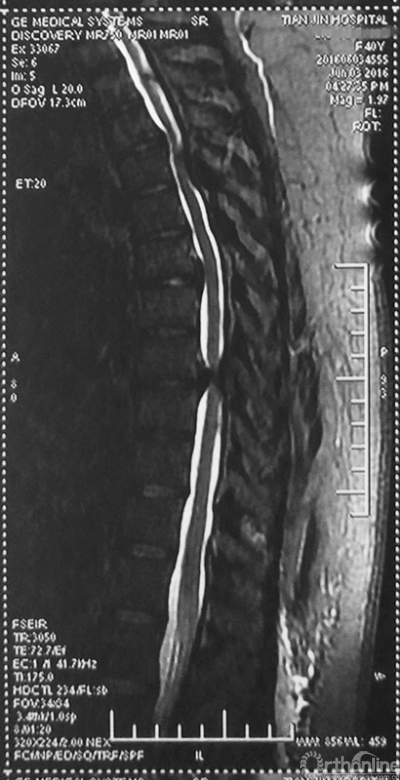

术前MRI

家人曾带她辗转当地治疗,因病情复杂没有得到有效的治疗,于是慕名找到天津医院脊柱外科二病区主任苗军博士诊治,当苗军主任看到躺在担架上的刘女士痛苦的表情和渴望健康的眼神,他决定收她入院为其进行手术治疗。入院检查发现,刘女士患有多节段胸椎管狭窄症,以胸8-9节段严重,椎管狭窄达80%,脊髓已严重变性。